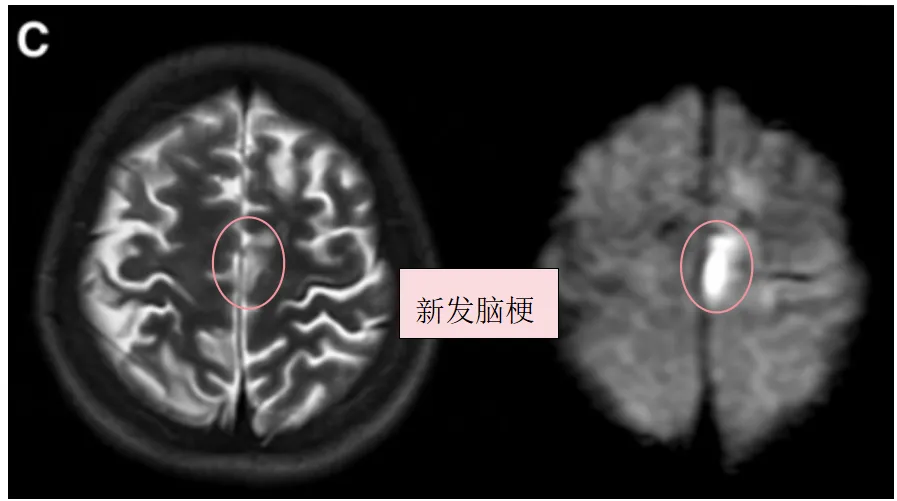

1个月后,幸子因构音障碍和右腿无力入院,并在左额叶出现新的脑梗死(图1C)。随后出现甲状腺风暴(fT4 3.91 ng/ml,fT3 10.09 pg/ml)——甲状腺机能亢进的合并症,是一种少见但能致死的病症。伴有发热、心动过速和高血压等甲状腺毒症症状。

▼C,术前T2、DWI序列显示左额叶新发展的脑梗死。

▼D,入院3天后术前T2、DWI序列显示左侧颞叶进一步新发脑梗死